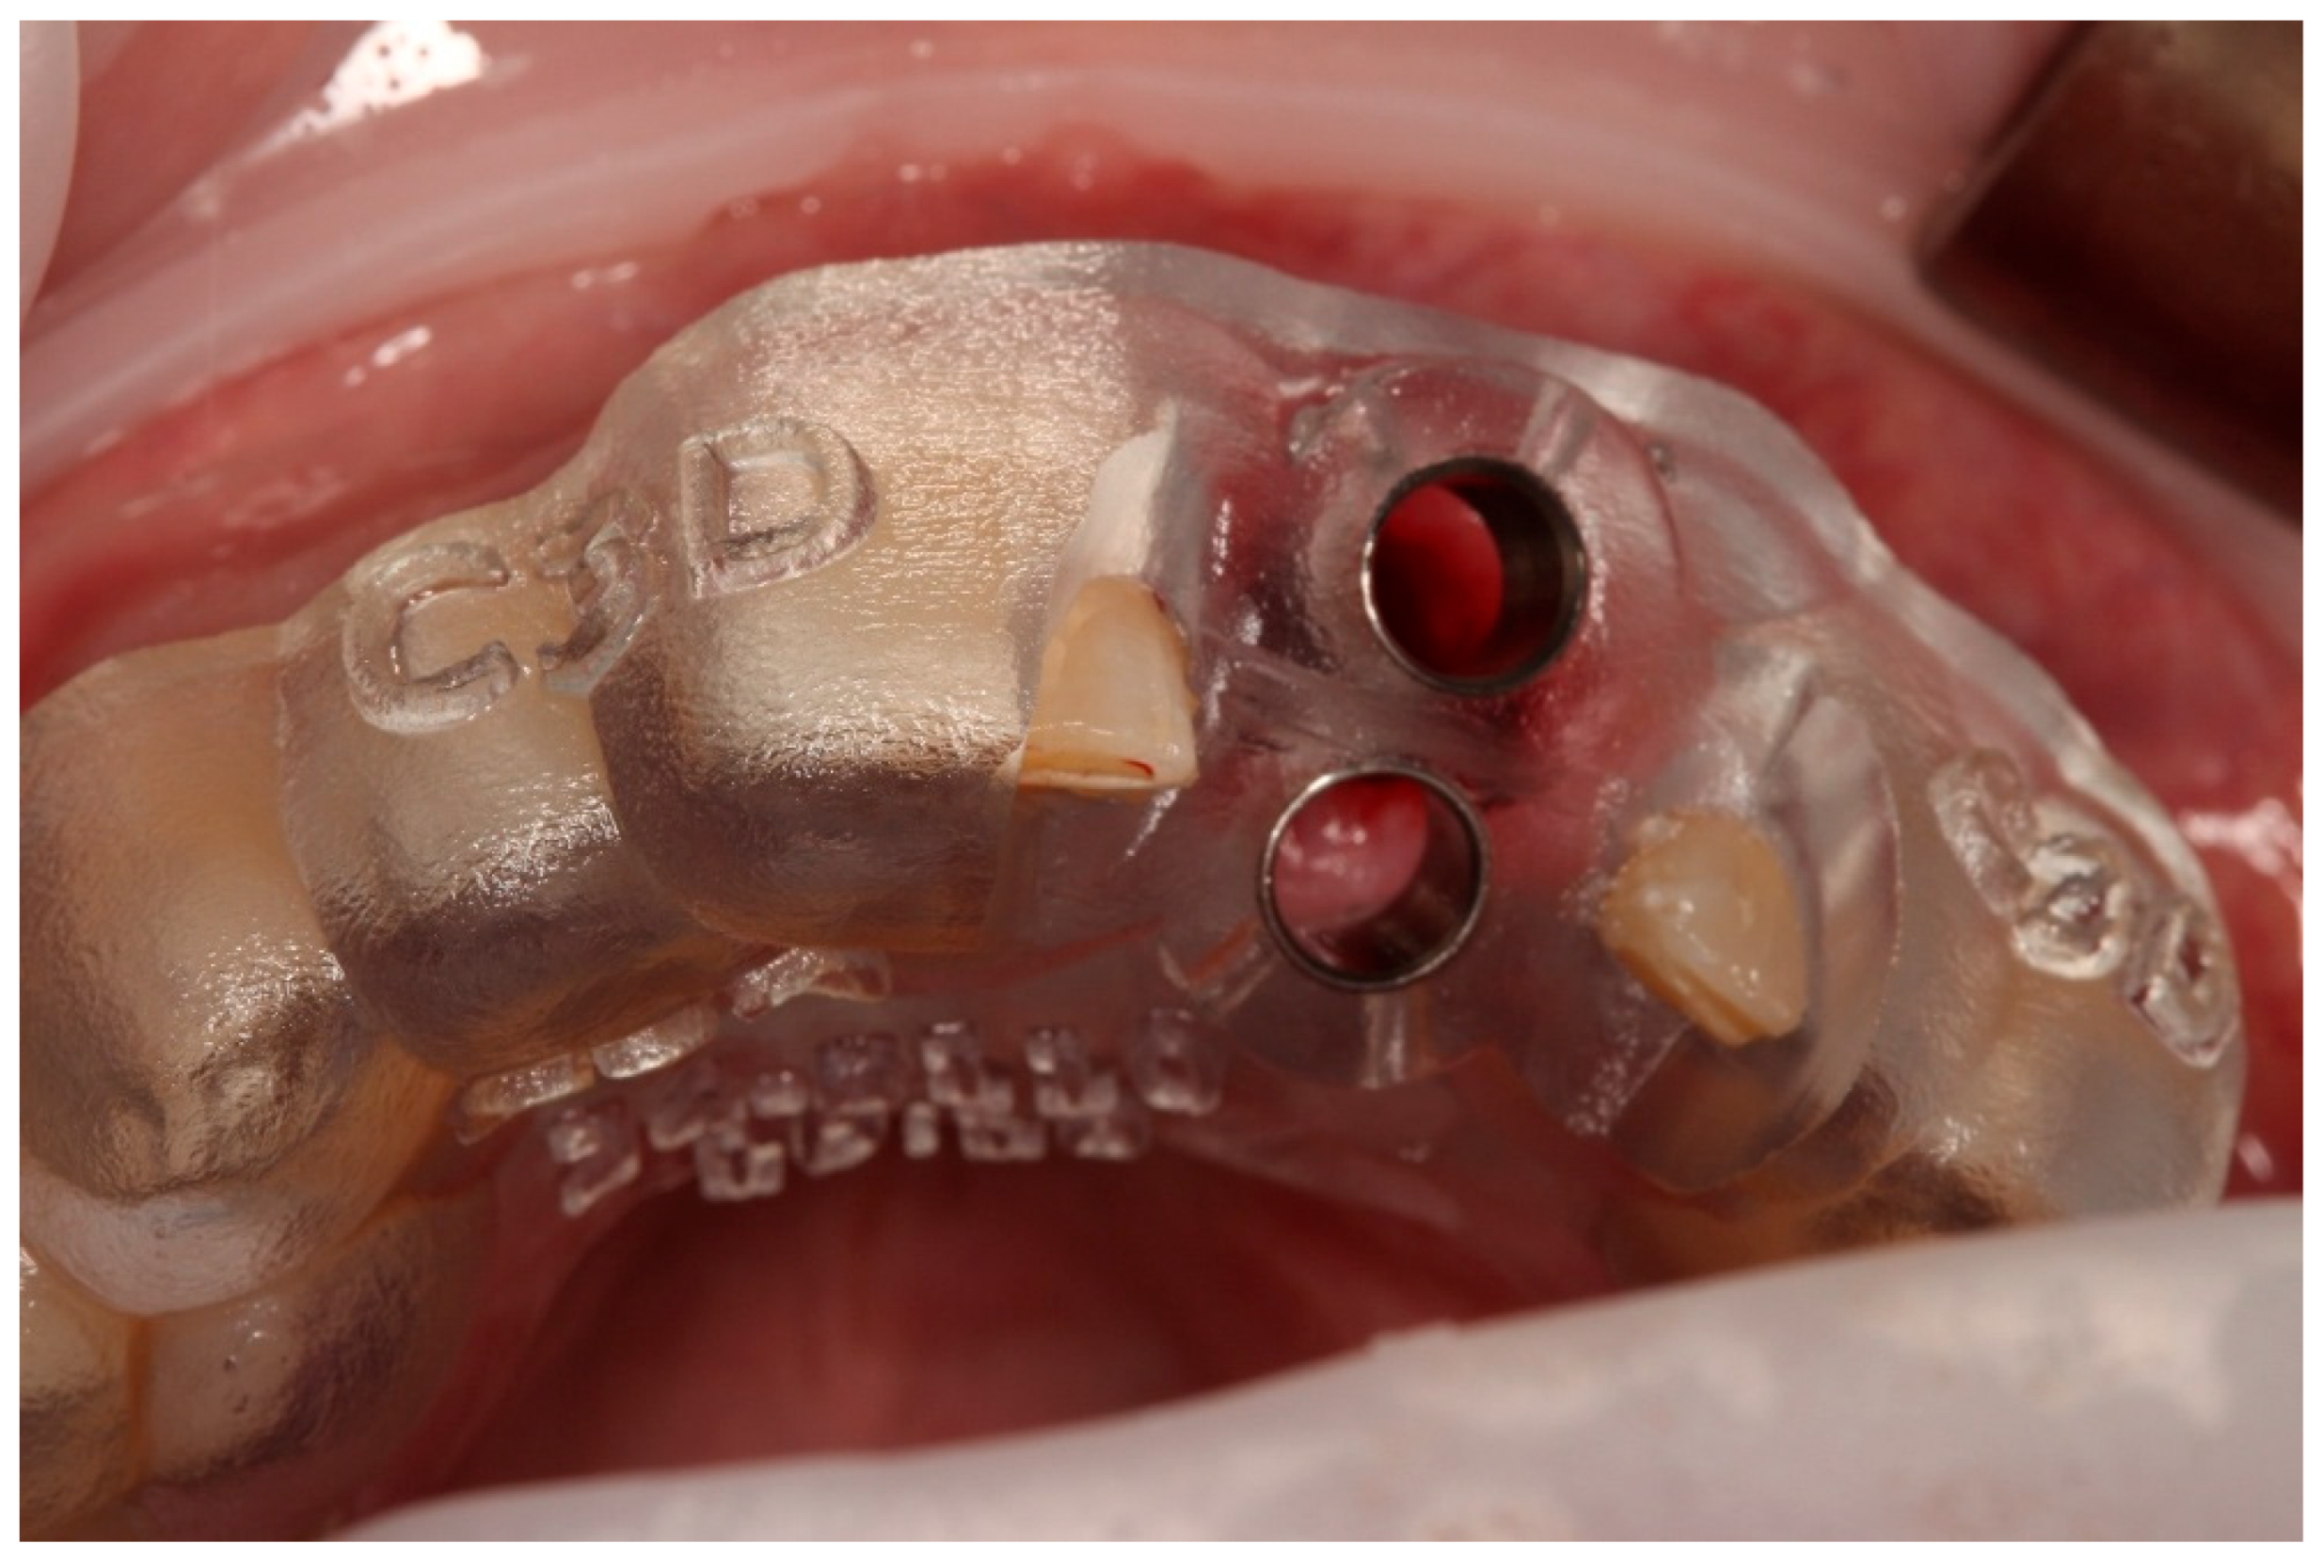

2.4. Digital Planning and Surgical Guide Fabrication

- Preparation of the recipient socket: After curettage of granulation tissue from the original socket, the CAD/CAM surgical guide was positioned. A guided osteotomy was performed using the implant-type drills from the C3D Cambados guided surgery kit, following the virtual plan. A biologic drilling protocol without irrigation was used to preserve autologous bone chips in the osteotomy walls. These chips were collected and later used as graft material. Drill sequence, diameters, and depth calibration followed the manufacturer’s recommendations and the digital plan, maintaining a stable trajectory and preserving palatal bone for primary stability.

- Verification with the 3D-printed replica: The printed tooth replica was inserted into the prepared socket to confirm angulation and depth prior to replantation of the original tooth.